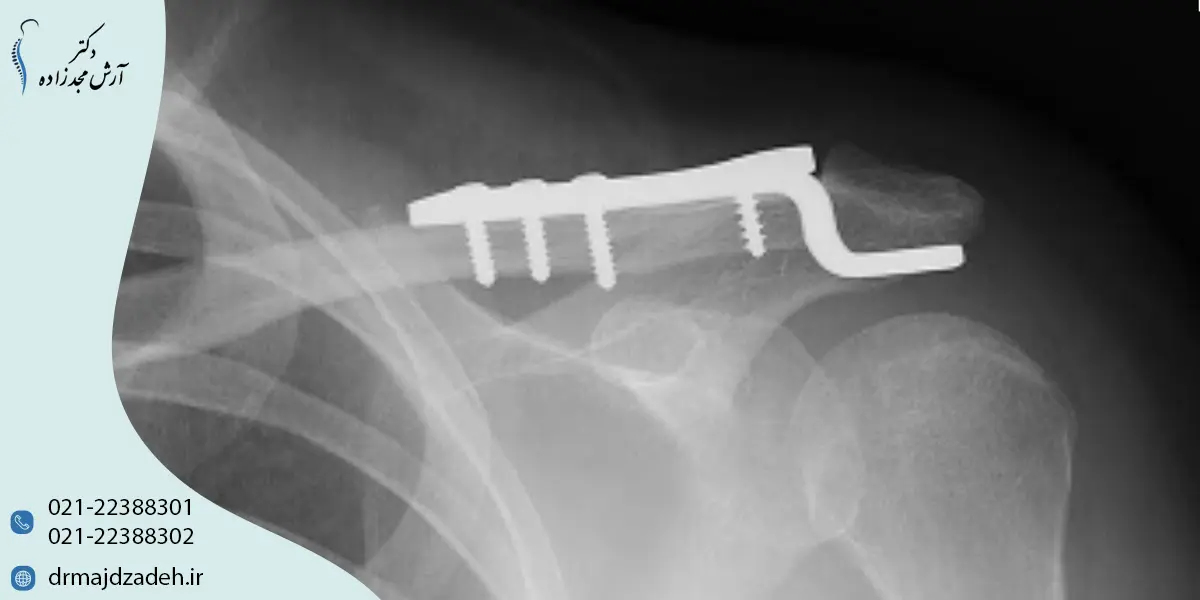

درمان جراحی شکستگی ترقوه

در شکستگیهای شدید، جابهجا شده یا همراه با آسیب عصبی، جراحی توصیه میشود. در این روش استخوان با پلیت یا پیچ تثبیت میشود.